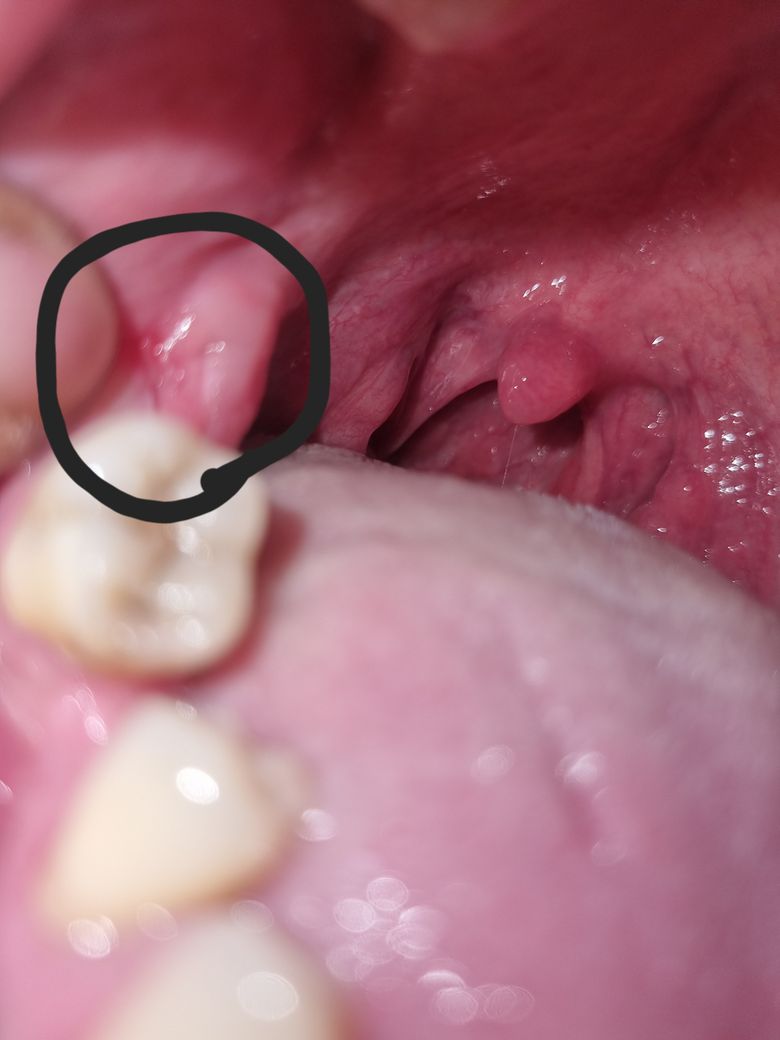

사랑니1년전에 발취한곳인데 잇몸이 아파서 들여다보니 저렇게 상처 같아 보이는게 생겼어요

자고일어나보니 잇몸이 아파서 들여다보니 저렇게 상처같아보이는게 생겼어요 잇몸이 파인거같아보이고 찢어진거같아보이고 왜그런걸까요? 큰병인가 걱정이 됩니다ㅠ

사랑니 1년전에 발취한곳인데 잇몸이 잘못된것일까요?

사랑니 발치한 부위는 잘 아문 것으로 보입니다.

약간 빨갛게 보이는 부위는 상처가 생겼거나 아니면 염증이 생긴 것으로 보입니다.

사진만으로는 정확한 판단이 힘들지만 아마 교합에 의한 외상(trauma)로 보여집니다. 즉 아래 위 치아가 맞물리거나 씹는 과정에서 해당 부위가 자극되어 일시적으로 상피에 손상이 가해진 것으로 보여집니다. 특별히 사랑니 발치로 인하여 나타난 것은 아니며 시간이 지나면 대부분 회복됩니다.

지금과 같은 일시적인 손상은 큰 치료 없이도 2주 안에 자연스럽게 회복되는 것이 특징입니다. 하지만 2주가 지나도 해당 부위에 통증이 있고 사진처럼 계속해서 손상이 있다면 이때는 정확한 진단을 위해 치과 방문을 하셔야 합니다.

사진이 흐려서 정확히 알 순 없지만, 위치아에 의해 씹힌 자국일수도 있고, 염증일수도 있습니다.